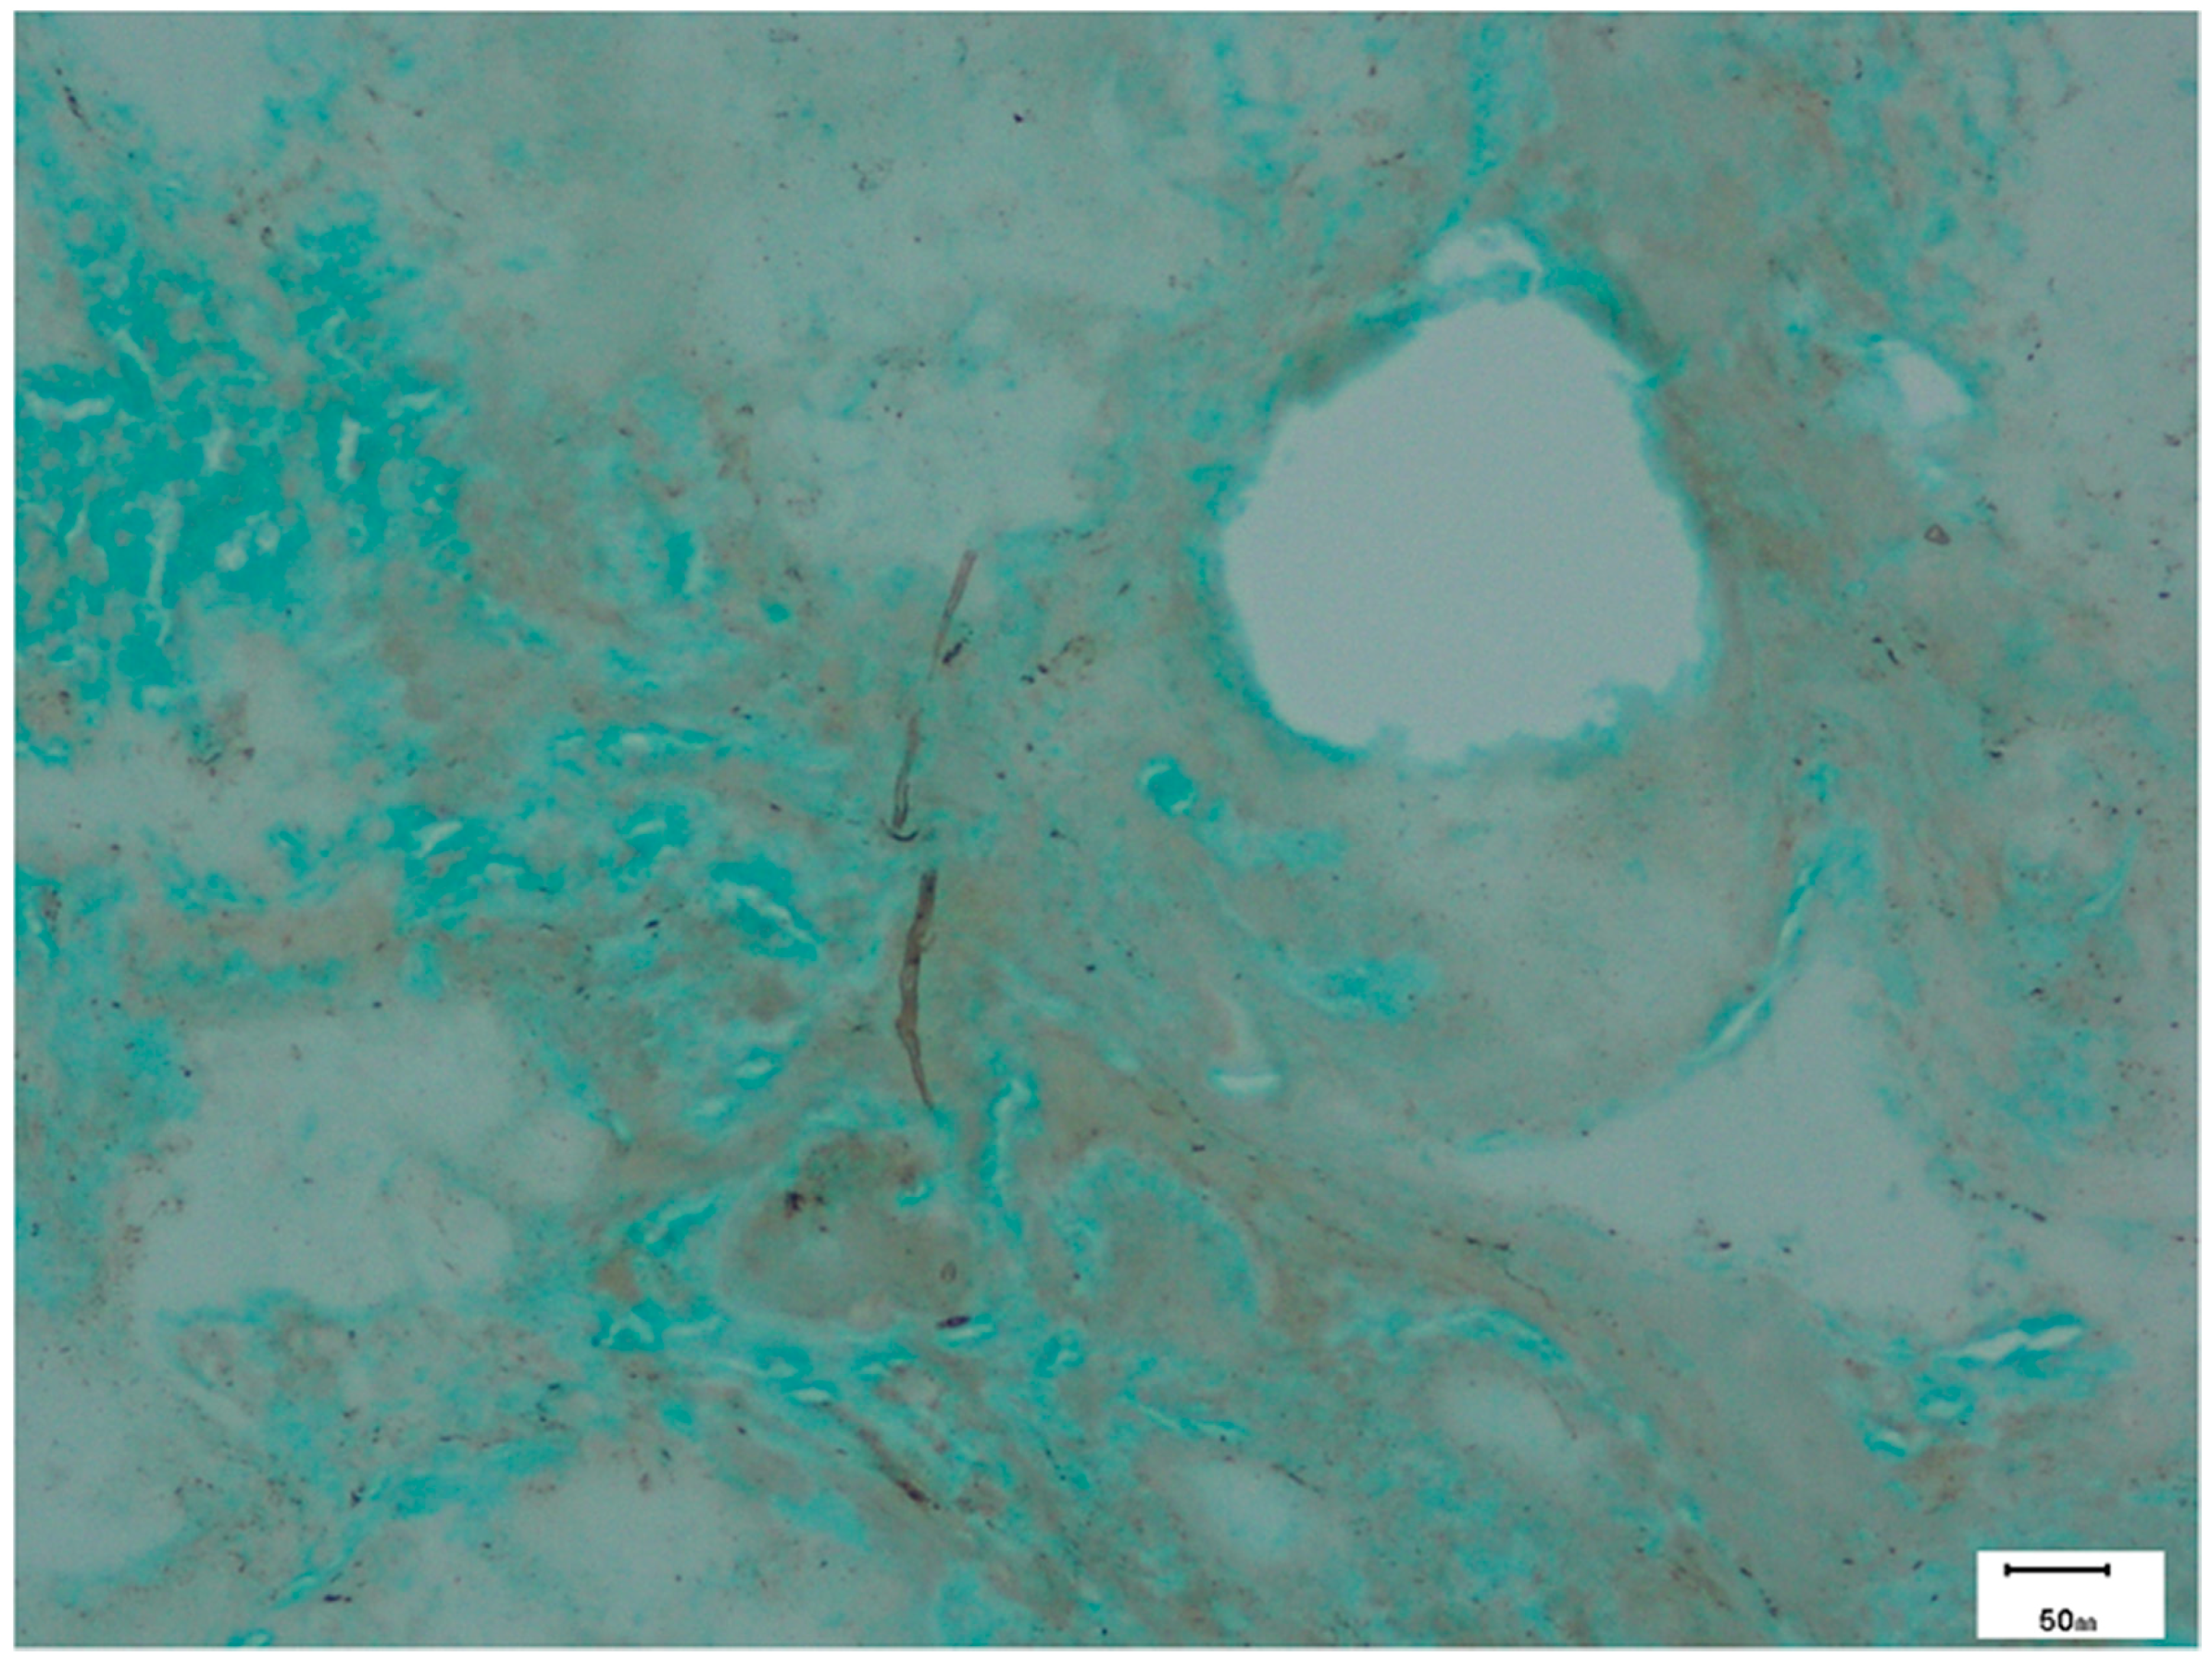

8.3. Pathology